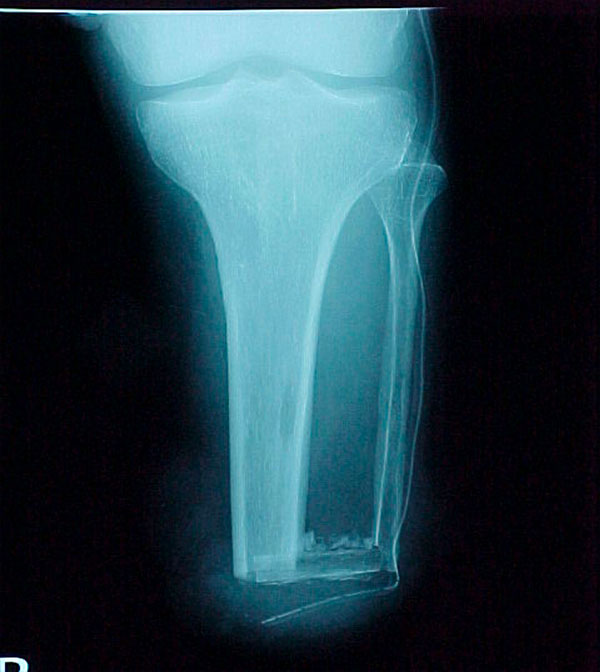

- Focus Area Reconstructive Surgery & Non-Surgical Management to Improve Bone Healing

- Primary Objective To define a serum protein based diagnostic for the progression and failure of fracture healing, though the identification of a set of serum proteins that appear at early times of biological healing and show a specific correlation with later radiological and functional signs used to define delayed healing and non-union.